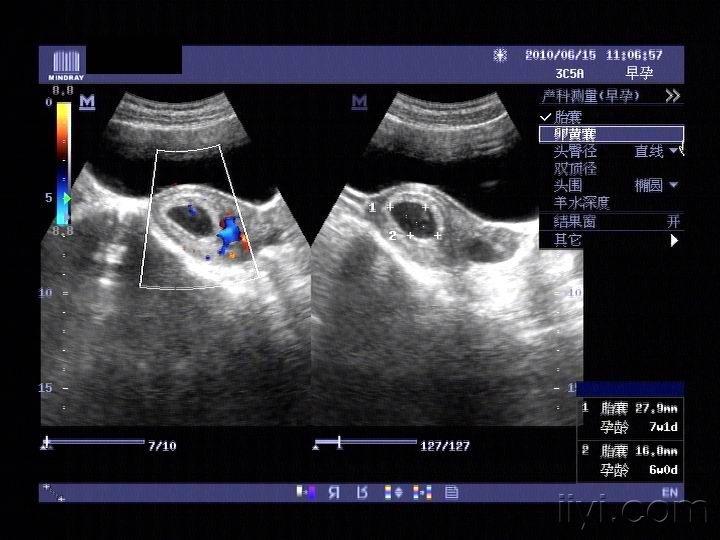

卵黄囊的彩超图片,卵黄囊是什么

有没有两个卵黄囊的

请问照彩超结果是双卵黄囊是双胞胎吗?

卵黄囊b超图

卵黄囊和胎芽图

卵黄囊图片孕囊

卵黄囊图片b超

b超下的卵黄囊图

正常的卵黄囊图片

卵黄囊图片

正常孕囊和卵黄囊图

卵黄囊胎心胎芽结构图

卵黄囊胚芽

卵黄囊

卵黄囊大小对照表

卵黄囊结构